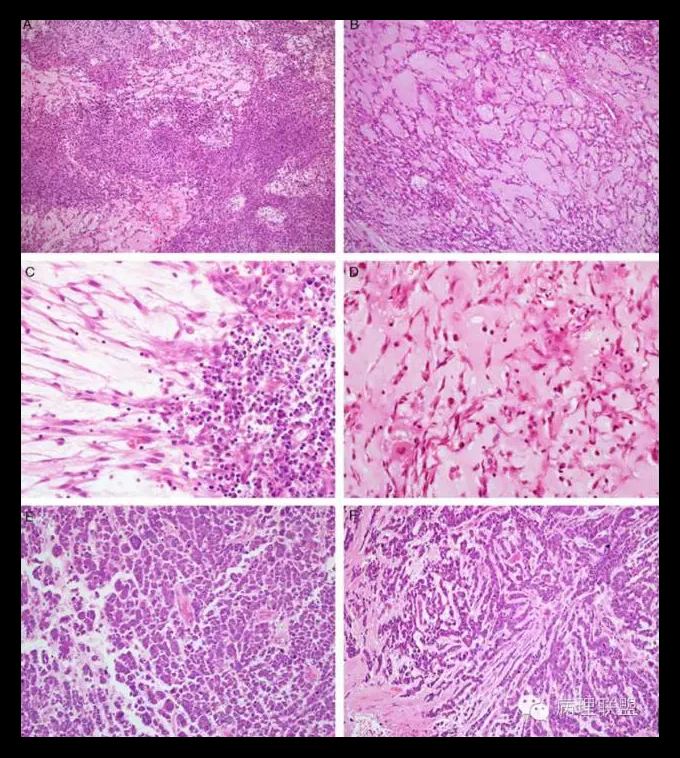

肿瘤位于支气管黏膜下,瘤细胞呈短梭形细胞、卵圆形细胞、多边形细胞和星状细胞,弥漫排列或呈条索状排列,间质呈黏液样。瘤细胞显示有一定的异型性,可见核分裂。形态学类似肌上皮肿瘤或骨外粘液性软骨肉瘤。

伴有EWSRl一CREBI融合性基因的肺原发性黏液样肉瘤(primary pulmonary myxoid sarcoma with EWSRl-CREBI fusion)